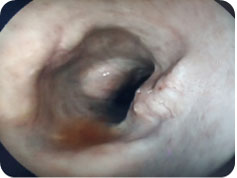

Endoscopy allows a visual examination of internal organs and body parts without invasive exploratory surgery, using fiber-optic instrumentation. Special video cameras attached to the endoscope allow viewing of the exam on a screen. The advantage of endoscopy over other methods is that it is less invasive.